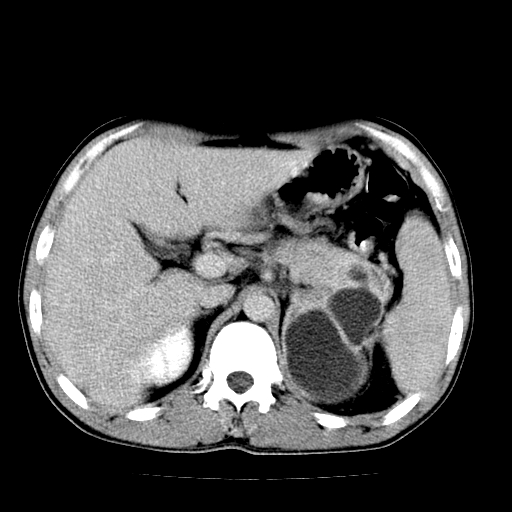

以下是引用天南地北在2007-4-30 13:36:00的发言:[br]支持慢性胰腺炎伴有假性囊肿

以下是引用andymaomao在2007-4-30 14:28:00的发言:[br]支持:1.慢性胰腺炎并假性囊肿形成可能;[br] 2.左肾形态稍增大,旋转不良。